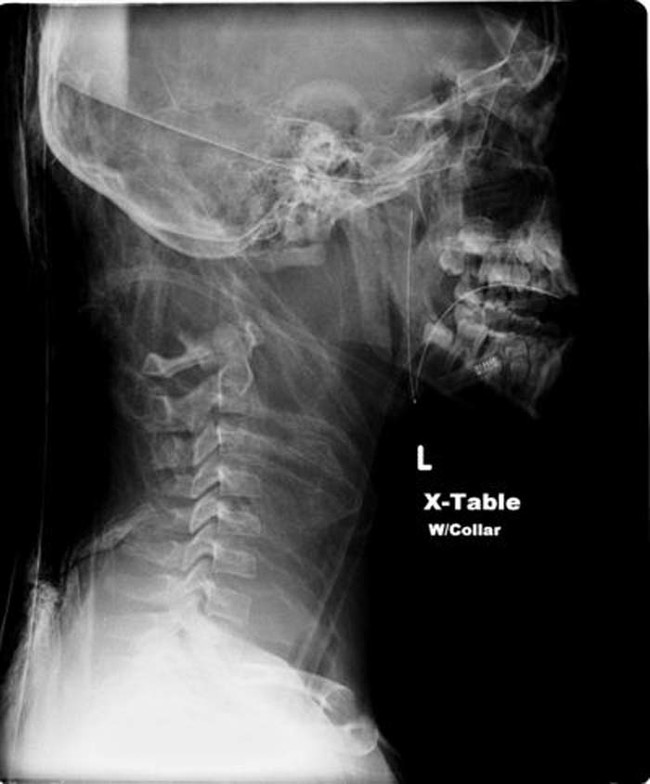

External decapitation is the kind that we’re all familiar with, an outside force severs the head from the body. Internal decapitation though, is much rarer and interesting. When someone is internally decapitated, their skull is severed from the spinal column, but is still attached to the body. This can be caused accidentally during severe head trauma, or intentionally. In fact, the act of hanging relies on the mechanism of internal decapitation to ensure that the victim dies quickly. While it might seem impossible, there have been a handful of people in recent history who have survived internal decapitation thanks to quick thinking doctors.